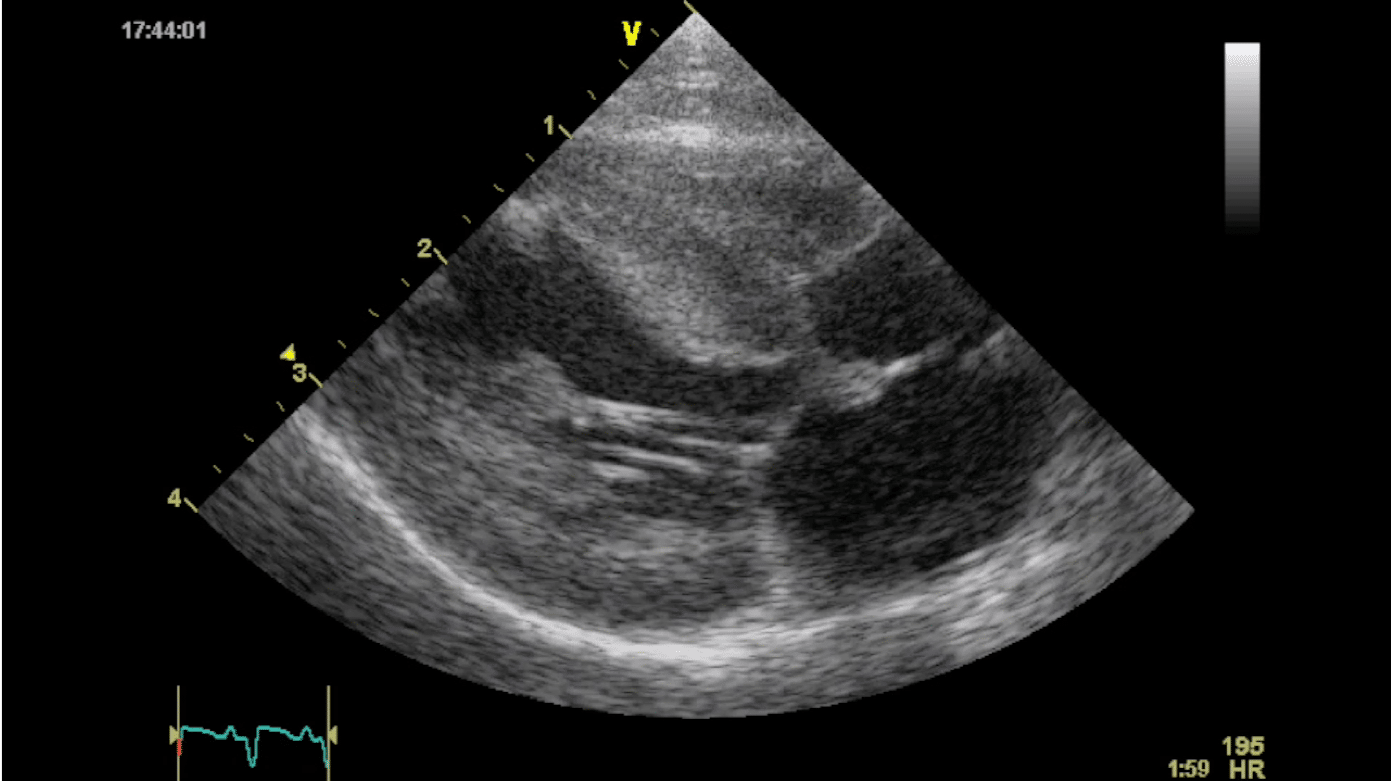

Echocardiography is the gold standard for diagnosing hypertrophic cardiomyopathy in cats. Elizabeth Rozanski, DVM, ACVIM, ACVECC, and colleagues at Tufts University knew that several barriers to this test exist including cost, proximity to a boarded cardiologist, and the skillset and equipment required to perform a full echocardiogram. They were also aware that focused cardiac ultrasound (FCU) was gaining popularity in human hospital emergency rooms as a quick way to assess patients for serious cardiac conditions. Dr. Rozanski wanted to determine if a non-specialist practitioner (NSP) could be trained to perform FCU to increase detection of occult heart disease in cats.

Dr. Rozanski and her team developed an FCU protocol and trained 22 NSPs to perform the procedure. The NSPs screened 289 cats without signs of heart disease. All patients had follow-up echocardiograms by a board-certified cardiologist.

Dr. Rozanski found that the NSPs were very good at detecting moderate and severe heart disease in the study population. They were less skilled at detecting mild disease, but Dr. Rozanski was encouraged by the results and hopes more practitioners can learn FCU and incorporate it into their practice. Dr. Rozanski published her results in the Journal of Veterinary Internal Medicine.